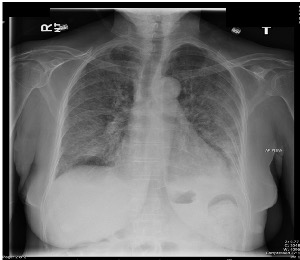

He was admitted for treatment of severe COVID and started on Methylprednisolone and Tocilizumab (anti-IL6-receptor antibody).